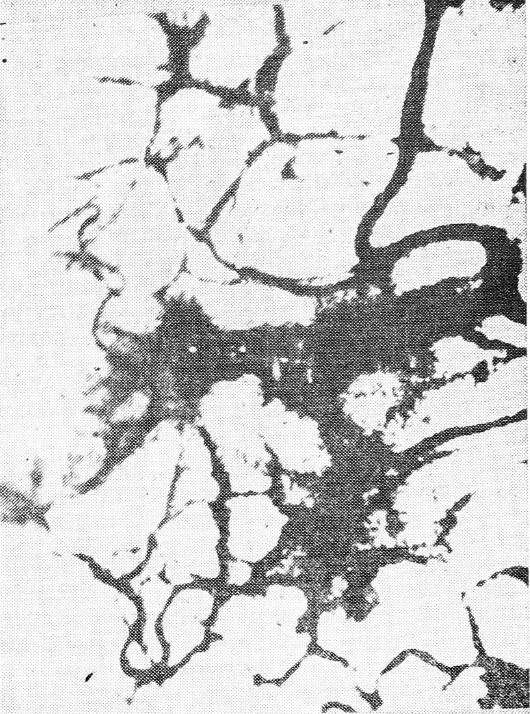

Рис. 9. Сосуды конъюнктивы глазного яблока

При осмотре сосудов конъюнктивы глазного яблока в 80% случаев отмечен выраженный периваскулярный отек, в 20 % — микрогеморрагии. У половины обследуемых женщин обнаружены зоны «запустевания» капилляров, бледность, «бедность» сосудистого фона, характерная «ячеистость», что связано с образованием артерио-венулярных анастомозов (рис. 9). Отношение артериол к венулам — 1/5, в 10% случаев — 1/7. У каждой пятой больной были аневризмы венул. Агрегация эритроцитов в тяжелых случаях наблюдалась в сосудах всех диаметров (в 30%), в венулах крупного диаметра, артериолах среднего и мелкого диаметра и капиллярах (в 20%).

После лечения уменьшался периваскулярный отек, увеличивалось число функционирующих капилляров (ФК); агрегация эритроцитов ограничивалась риолами мелкого диаметра; в 80% случаев кровоток в капиллярах оставался нарушенным.